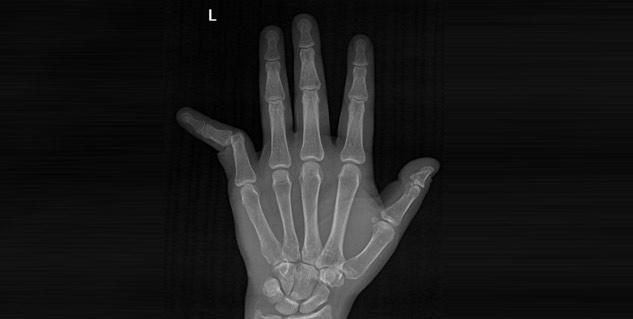

Well it is not hard to determine condition of finger dislocation but there is a need to understand the adversity of the dislocation that has occurred. Once there is enough evidence to know that the condition is finger dislocation, it becomes easier to treat it in the best way possible. Normally X-ray is taken to rule out the chances of having fracture.